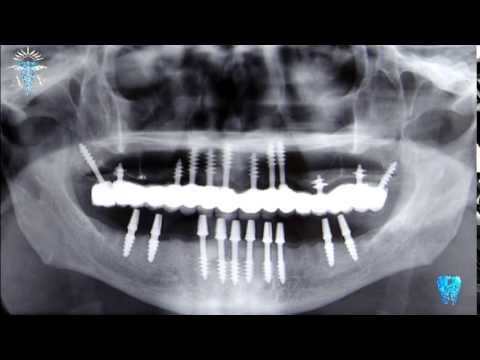

Рентгенова снимка на поставени базални импланти. Според много компании, които произвеждат зъбни импланти от този тип, те са удачни за приложение в анатомични области с намален костен обем. Това твърдение до голяма степен отговаря на истината и, подобно на хибридната пропаганда на режима на Путин, подвежда много зъболекари да поставят базални импланти - известно е че хората вярват много повече на полуистини, отколкото на откровени лъжи. Наистина, много видове базални импланти се характеризират с малък диаметър и могат да бъдат поставяни в изключително тесни алвеоларни гребени. Голямата дължина на подобни видове импланти позволява те да навлизат в невероятни анатомични области - птеригоидни израстъци, на мястото на канинови зъби в латералните стени на носната кухина (респективно в медиалната стена на максиларния синус) и много други. Проблемът е че в огромна част от клиничните случаи това поставяне не се извършва чрез сложни навигационни триизмерни методи (хирургични водачи), а чисто умозрително и по усет - имплантът се завинтва смело навътре, до момента в който затегне. Поради това, както се вижда на горната рентгенография, една част от зъбния имплант се разполага в пределите на костната тъкан, а друг - в меките тъкани или съвсем във въздушна среда в обема на максиларния синус. Очевидно е че нито меките тъкани, нито въздухът в максиларния синус са в състояние да осигурят адекватна задръжка на импланта и съответната механична устойчивост.

Друга рентгенография на поставени базални импланти. В областта на долната челюст има достатъчно костен обем, докато при горната той е силно редуциран. Базалните импланти осигуряват възможност за поставяне с последващо протезиране дори и от колеги, които нямат клиничен опит в повдигането на пода на максиларния синус (синус лифтинг); нерядко дори и от такива, които дори не могат да поставят един хирургичен шев. Крайният резултат от подобни лечения обаче не винаги е траен и задоволителен - както вече беше споменато в началото на настоящото изложение, именно костната тъкан осигурява добра задръжка на импланта в триизмерното пространство. На горната рентгенография се вижда как някои импланти на горната челюст са разположени частично извън пределите на костта - което според почитателите на този тип лечение не представлява проблем, тъй като друга част от импланта пък определено е в пределите на костта и това осигурява добра механична задръжка. Ситуацията силно наподобява мисленето на оптимистите и песимистите - според първите чашата е наполовина пълна, а според вторите - наполовина празна. Позитивното мислене е в състояние да промени нагласата на всеки един човек към живота и да го извади от депресивни състояния и мисловни ями; само по себе си обаче то не повлиява с нищо върху реалността - за това се изискват активни действия. Именно тук се намесват реалистите; според друго сравнение песимистът не вижда светлина в тунела. Оптимистът вижда светлина в тунела, но реалистът осъзнава че тя всъщност се излъчва от фара на приближаващия товарен влак. Машинистът пък вижда трима не особено адекватни индивида, които стоят и обсъждат нещо върху релсите - нещо подобно се получава и при имплантологичните провали, особено при големи мостови протези.